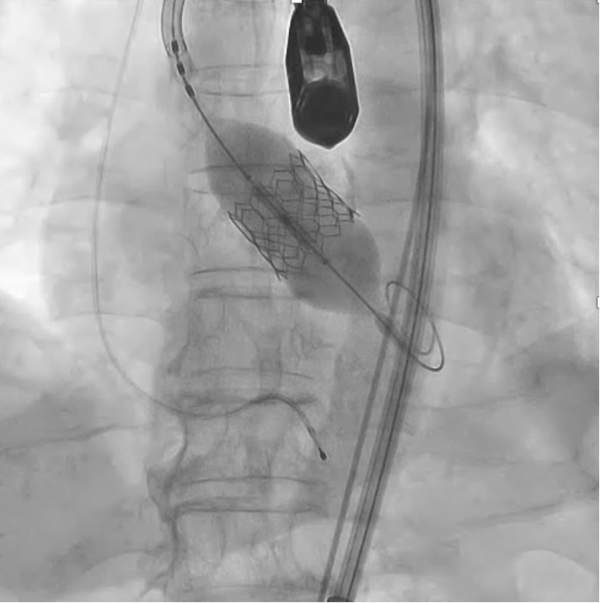

• TAVI風景

高齢の患者さんにも安心して受けていただける低侵襲TAVI(経カテーテル大動脈弁置換術)。「こんな治療ができるんだ!」と驚く、感動の現場を間近で体験できます。

• TAVI弁留置

最先端デバイスを手に取り、自分の手で大動脈弁を留置する貴重な一瞬。目の前で動くリアルな解剖モデルを相手に、確かな手応えと自信を得られます。